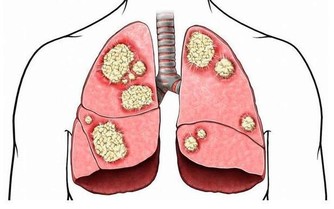

酒精對身體的危害十分廣泛包括心腦血管、中樞神經、消化系統、肝膽脾胃等,我下面著重介紹一下不大多見,與酒密切相關一種病,馬德龍病。

馬德龍綜合徵是一種因長期飲酒,導致脂肪代謝紊亂,在皮下等部位對稱、過度堆積而形成一種病症。脂肪常會堆積在頭部、頸部、肩部以及腰部等部位,上下肢呈現近端肥胖、遠端細小,類似動漫“大力水手”的手臂外形。

患者常因堆積脂肪組織壓迫氣管、食管,出現呼吸困難和吞嚥受阻而就診。

發病特點,多為男性,有長年飲酒史,有的飲酒史長達20到30年之久,飲酒量大,每天飲酒在1.5斤至2斤。

隨著生活水平提高,飲酒者不斷增加,該病有增多趨勢。

目前馬德龍病治療,關鍵在於戒酒。

堆積脂肪可通過外科手術分期切除,或吸脂的方式進行清除,但這只是對症治療,不是根治之術,若患者不下決心徹底戒酒,復發只會是早晚的事。